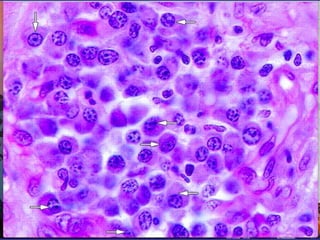

células plasmáticas

Derivadas de los LINFOCITOS B

En los tejidos conjuntivos su vida media es de

10 a 20 días. Su función es sintetizar y secretar

los anticuerpos (proteínas )

inmunoglobulinas. Ig

Su número aumenta en los tejidos con

procesos inflamatorios crónicos (parasitismo).

Abundan en la mucosa digestiva,

incrementándose durante la digestión, en los

órganos genitales durante el embarazo

• Forma redondeada

u ovalada

• Citoplasma

basófilo

• núcleo excéntrico,

redondo y de

heterocromatina

dispuesta en

grumos radiales

• Móviles

La penetración en el organismo de

moléculas extrañas, que reciben el

nombre de antígenos, estimulan la

diferenciación de los linfocitos B en

plasmocitos y la producción por estas

células de anticuerpos, como

respuesta específica a los antígenos.

A-Celulas plasmáticas inflamación crónica

B- Inflamación aguda neutrófilos

C- Intestino delgado eosinofilos